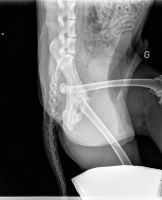

Voici les radios du 23 octobre... la tête du fémur est nécrosée...sur problème infectieux... je ne suis pas contente... la seule alternative qu'il reste maintenant et de tout enlever, de couper la tête du fémur... et Twarak devra vivre ainsi.

Il me dise que pour un chien comme lui, c'est très gérable... je suis triste pour Twarak....